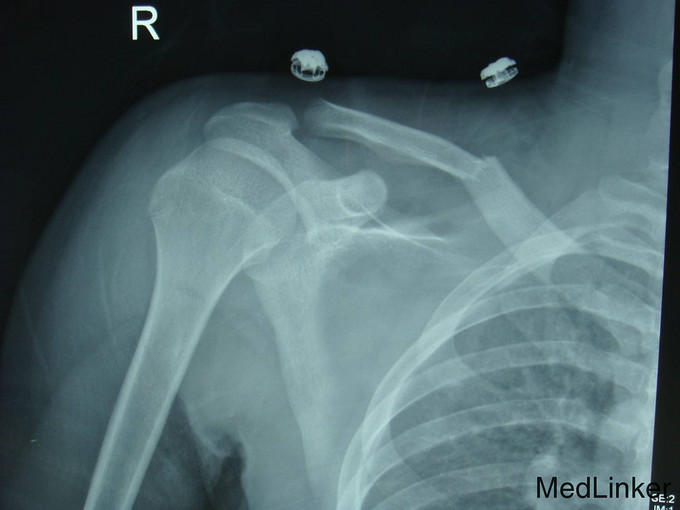

患者自述于2014年6月2日晚上走路时被出租车撞倒,伤后自觉右肩关节疼痛活动受限,于当地医院就诊,拍DR示:右锁骨骨折,今为求进一步系统治疗来我院,行相关检查后,急诊以“右锁骨骨折”为主要诊断收入我科,伤后无一过性昏迷,无头痛,无恶心呕吐,无发热、咳嗽咳痰、乏力、盗汗,体重最近无减轻,饮食可,二便正常。

专科检查:有上肢吊臂带固定中,有侧锁骨中段可见畸形,可触及骨擦感,压痛(+),肿胀,左肩活动受限,右上肢无明显麻木,桡尺动脉清楚,各手指感觉活动可。

诊断:右锁骨骨折(Allman I) 患者入院后完善检查,查无手术禁忌症后行右锁骨骨折切开复位钢板内固定术,术后6小时后患者下地行走,术后第二天出院。